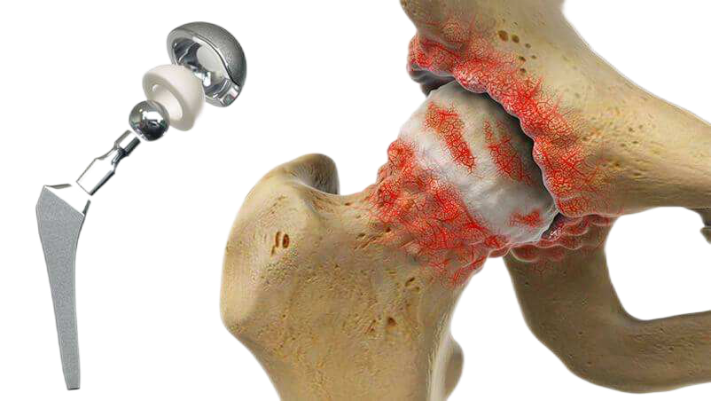

对于晚期股骨头坏死病人来说,人工全髋置换术是最有效地缓解疼痛、改善髋关节活动度和恢复正常日常生活的手术方法。

对于出现骨性关节炎的患者,只能将关节置换作为最佳选择。由于此类患者关节置换效果较其他患者差,因此在出现骨性关节炎前,采取各种保存股骨头的治疗方法延缓病程的发展,推迟全髋置换的时间仍有必要。

颍上县人民医院骨科二病区(原骨科三病区)能够自主开展全髋关节置换术、人工股骨头置换术、全膝关节置换、膝关节单髁置换及微创膝关节镜技术等关节手术,全体医务人员将以科学的诊疗技术、优质的服务理念,竭尽所能为每位患者排忧解难,为百姓健康保驾护航,全心全意为人民服务。